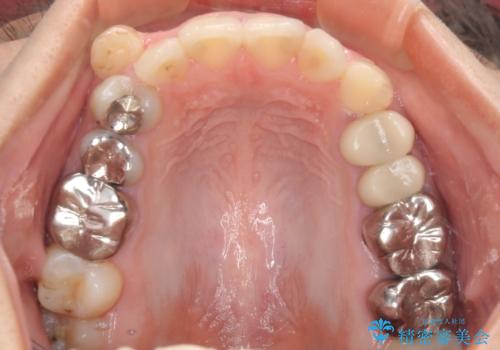

結婚式前に目立つ銀歯をセラミックに

- 笑ったときに見てしまう上顎奥歯の銀歯を気にして来院された患者様です。

他にも目立つ銀歯がありましたが、最も気にしている2本を優先して行うこととしました。